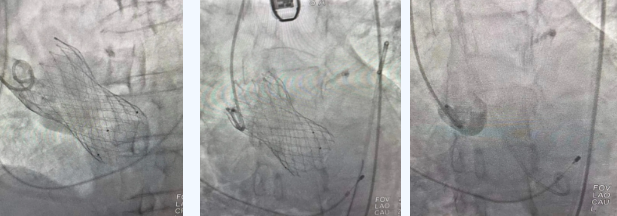

在麻醉手術(shù)中心的配合下,曾廣偉主任用導(dǎo)管經(jīng)股動脈鞘進入主動脈瓣目標(biāo)位置,經(jīng)豬尾導(dǎo)管造影可見主動脈瓣大量返流,因左室流出道較寬,大于瓣膜落腳點直徑,瓣膜釋放位置選擇及釋放難度極大。更為關(guān)鍵的是,患者常規(guī)四個錨定點只有一個可以用,定位要極其精準才能保證瓣膜釋放后牢靠,同時不能有大的殘余瘺!稍有移位可能就需要再次植入瓣中瓣或者開刀!

術(shù)中,曾廣偉主任團隊高效配合,完成了特定時間點起搏心臟、臨時短時間關(guān)閉呼吸機、降低主動脈瓣阻力、快速釋放瓣膜等一系列高難度操作,有效保證瓣膜精準釋放。瓣膜釋放經(jīng)TEE確認,主動脈瓣膜釋放位置佳,經(jīng)豬尾導(dǎo)管造影,主動脈瓣返流即刻消失,且無瓣周瘺。